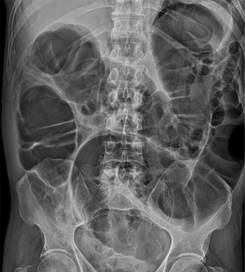

Al cursar el día nueve de ingreso hospitalario, presentó distención abdominal, por lo que se indicó permeabilizar sonda nasogástrica y mantener a derivación, así como el retiro de la nutrición enteral. Tras 48 horas sin presentar mejoría al manejo conservador, y agregándose ausencia de evacuaciones, se solicitó estudio tomográfico abdominopélvico reportando hallazgos en relación con importante dilatación colónica (Figura 1), se solicitó valoración al servicio de cirugía general por los hallazgos tomográficos, resaltando la importancia del diámetro colónico. Y por representar un riesgo incrementado de perforación intestinal se decidió ingresar a quirófano para resolución quirúrgica, se realizó hemicolectomía derecha, colocación de ileostomía tipo Brooke, con un tiempo quirúrgico de cinco horas con los siguientes hallazgos: colon ascendente con incremento de diámetro (12 cm), colon transverso dilatado (8 cm), a nivel de ciego con dilatación importante (9 cm) y pared friable, se excluyó algún fenómeno de obstrucción mecánica en trayecto colónico.

La radiografía simple de abdomen en dos posiciones sigue siendo un método de diagnóstico útil para valorar la existencia de dilatación o distensión colónica con presencia masiva de gas en el colon y una distensión moderada del intestino delgado; ausencia de niveles hidroaéreos y edema en la pared hacen sospechar que no se trata de una simple obstrucción mecánica y orienta al diagnóstico de pseudo-obstrucción (Figura 3). Por otra parte, la presencia de neumoperitoneo confirma la existencia de una perforación intestinal.1,11,12

El estudio de imagen ideal sigue siendo la tomografía computarizada (TC) abdominal y pélvica con contraste intravenoso, mostrando una sensibilidad del 96% y una especificidad del 93%. Este método diagnóstico confirma la existencia de una dilatación colónica proximal y excluye otros tipos de obstrucción. La presencia de neumoperitoneo, líquido libre o neumatosis intestinal que se asocie con un colon distendido en la tomografía nos puede llevar a la fuerte sospecha de que se trata de una perforación colónica y esto indica una cirugía de laparotomía urgente.13

Nuestro caso clínico refuerza la asociación a factores de riesgo documentados en la literatura, la pronta sospecha clínica y bioquímica apoyada por el gabinete de imagenología fue pieza fundamental, los hallazgos (Figura 4) en relación a la dilatación colónica brindaron armas suficientes para iniciar el tratamiento farmacológico, teniendo en cuenta el límite superior de diámetro reportado en otros casos con presencia de perforación intestinal, por lo cual la colaboración de un equipo multidisciplinario y la toma de decisiones e intervenciones oportunas incrementaron nuestra tasa de éxito, favoreciendo el pronóstico y desenlace.